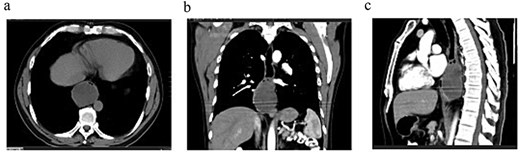

Endoscopic biopsies were negative immunostaining for DOG1 and CD117, ruling out a GIST, but positivity for actin with nuclear atypia, suggesting a smooth-muscle tumor of uncertain malignant potential. Contrast-enhanced computed tomography (CT) scan (Fig. 3) showed a 67 × 51 × 47 mm lobulated intraesophageal lesion with central necrosis and strong enhancement, originating from the posterior esophageal wall and nearly occluding the lumen, without regional lymphadenopathy, local invasion, or metastases.

Contrast-enhanced thoracoabdominopelvic CT scan: (a) axial section showing an oval intraesophageal mass; (b) coronal section illustrating the longitudinal extent of the tumor; (c) sagittal section showing a tumor apparently respecting the pericardium.